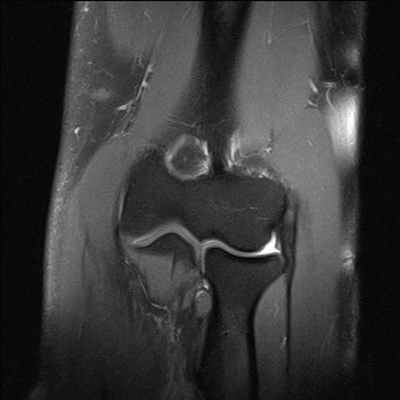

Способ проиллюстрирован чертежами, поясняющими сущность и эффективность заявляемого способа. На фиг.1 - оперативный доступ к сухожилию длинной малоберцовой мышцы в области наружной лодыжки; на фиг.2 - чрезоперативный доступ, теновыделителем проксимально отсекают сухожилие длинной малоберцовой мышцы от мышечного брюшка и выводят сухожилие в область операционной раны; на фиг.3 - отсеченное сухожилие длинной малоберцовой мышцы на препаровочном столике; на фиг.4 - схематично представлено направление проведения каналов, сухожилия и его крепление интерферентными шурупами в мыщелках большеберцовой и бедренной костях, трансоссальная фиксация в головке малоберцовой кости;

на фиг.5 - рентгенограмма коленного сустава в прямой и боковой проекции больного с начальными признаками остеоартроза; на фиг.6 - магнитно-резонансная томография коленного сустава больного, где отсутствует передняя крестообразная связка и наружная боковая связка; на фиг.7 - магнитно-резонансная томография коленного сустава больного, где показана восстановленная передняя крестообразная связка и наружная боковая связка; на фиг.8 - полное сгибание коленного сустава через три месяца после операции; на фиг.9 - стабильность коленного сустава через три месяца после операции.

На МРТ левого коленного сустава до операции в боковой и фронтальной проекциях - отсутствие ПКС и дефект НБС (Фиг.6).

На МРТ левого коленного сустава после операции в боковой и фронтальной проекциях: 10 - пластическое восстановление ПКС дупликатурой сухожилия длинной малоберцовой мышцы, 11 - пластическое восстановление малоберцовой коллатеральной связки сухожилием длинной малоберцовой мышцы, 12 - интерферентные шурупы (Фиг.7).